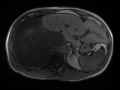

Dedifferentiated Retroperitoneal Liposarcoma

56-year-old male with chronic right-sided abdominal pain demonstrating a large, circumscribed, predominately cystic mass with T1 hypointense signal, T2 hyperintense signal, with nodular components that demonstrate heterogeneous, gradual enhancement. The lesion invades the right hepatic lobe of the liver. There is leftward shift of the caudate and left hepatic lobe as well as the hepatic IVC and portal venous system. At biopsy, the lesion was found to represent a dedifferentiated retroperitoneal liposarcoma. Retroperitoneal liposarcoma are a subtype of the liposarcoma tumor classification. Retroperitoneal liposarcoma represent one of the most common primary retroperitoneal neoplasms. Five histologic types including well-differentiated, myxoid, pleomorphic, round cell, and dedifferentiated.